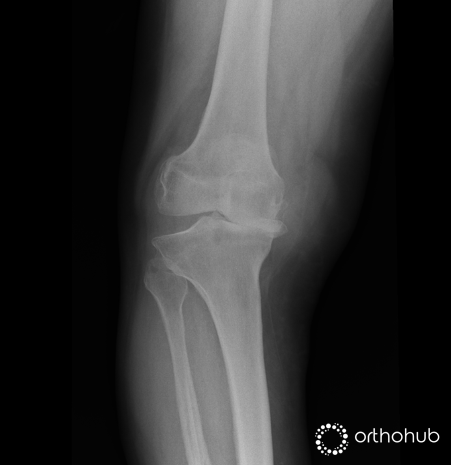

The radiographs are of a 62-year-old male, otherwise fit and well, who presents with worsening pain and stiffness in the joint. This is now increasingly limiting his day-to-day activities; including both his keen hobby of golf, and his work as a train conductor.

He reports having always ‘been a little bow-legged’ but was pain free until about 5 years ago. Physiotherapy and analgesia have failed to improve his symptoms. He takes no regular medication.

Clinical examination demonstrates pain and crepitus through the arc of motion, with marked laxity on varus stressing. The medial soft tissues are tight, and the patella tends to track medially. He is keen on a definitive surgical solution.